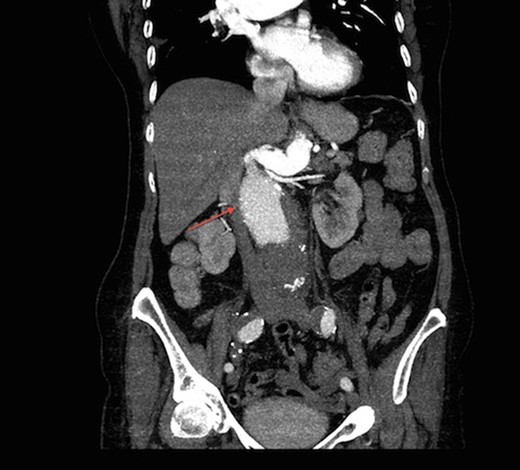

On arrival at our hospital, she was hemodynamically stable, with all vital signs within the normal range. Abdominal examination revealed a pulsating mass in the center of the abdomen. A computed tomography (CT) angiogram of aorta was performed for further evaluation that showed ectatic aorta from arch to the diaphragm. There was an 8.7-cm infra-abdominal AAA with extension into both common iliac arteries. The aneurysm neck was tortuous with an acute angle making endovascular repair challenging (Figs 1–4).

Transverse view of CT aortogram, showing compression of IVC (arrow).

Coronal view of CT aortogram showing compression of IVC (asterisk).